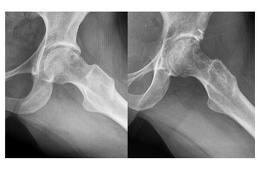

En su diagnóstico, las radiografías revelan las imperfecciones óseas y la resonancia magnética nuclear ayuda a visualizar las posibles lesiones del labrum (anillo cartilaginoso que rodea al acetábulo). El scanner 3D ayuda a visualizar con mayor exactitud la giba o imperfección ósea. A la vez que también se puede utilizar tomografía axial computada para ver esta zona.